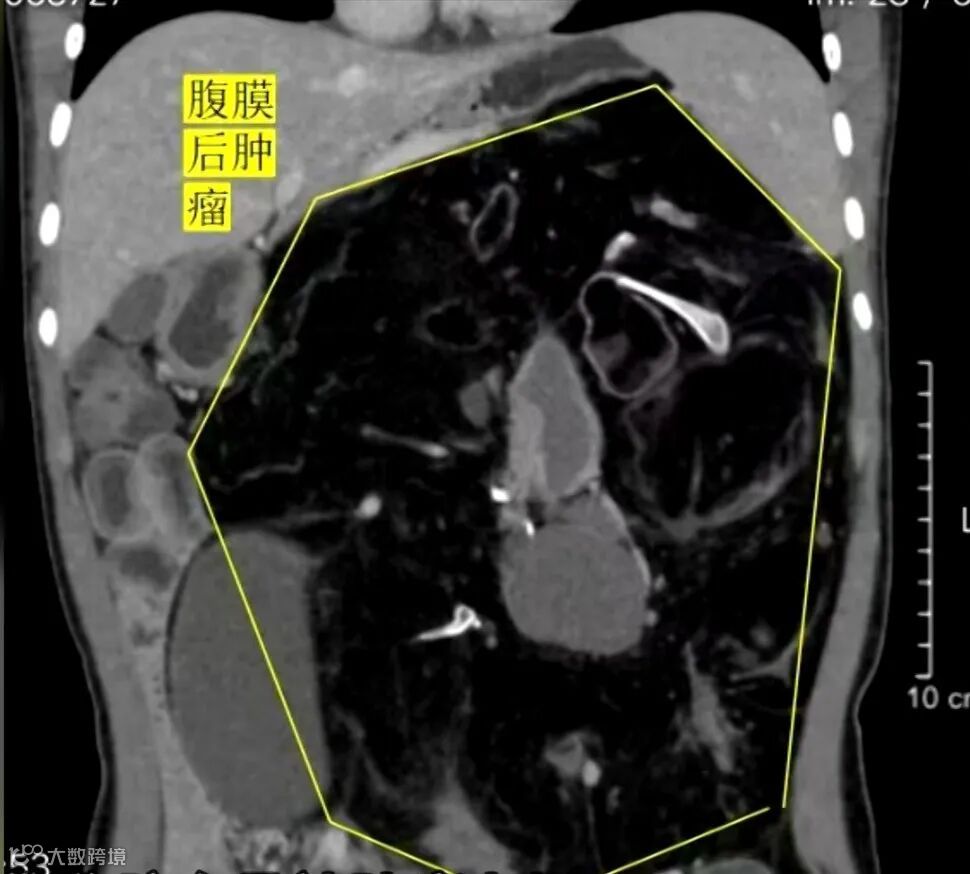

云南省第三人民医院肝胆胰外科主治医生 陈伟:“就是挺吃惊、挺大,而且整个脏器被肿瘤挤到了右上腹,整个左边还有盆腔全部被肿瘤占据。肿瘤差不多有40-50厘米左右的一个大小,它是一个圆形的,容积的话估计有个4-5升左右了。”

云南省第三人民医院肝胆胰外科主治医生 陈伟:“主要是两点,一个是肾动脉和脾动脉在肿瘤里边穿行,当时也和家属及她本人谈过,有可能她肾脏和脾脏都要放弃,为了切除这个肿瘤嘛。然后手术当中也是在肿瘤里边把它穿行的血管给剥出来了,所以还是把她的脏器都保留了。她肾动脉是被肿瘤侵蚀在里面,那一段我们是做了切除,然后给她重建了,最终还是把她的脏器功能保留了。”

经过四五个小时的精准操作,女生体内重达5.04公斤的“定时炸弹”被成功取出。其他曾经被肿瘤挤压变形的胃、肠管、脾脏和肾脏等脏器,均恢复到了正常位置。